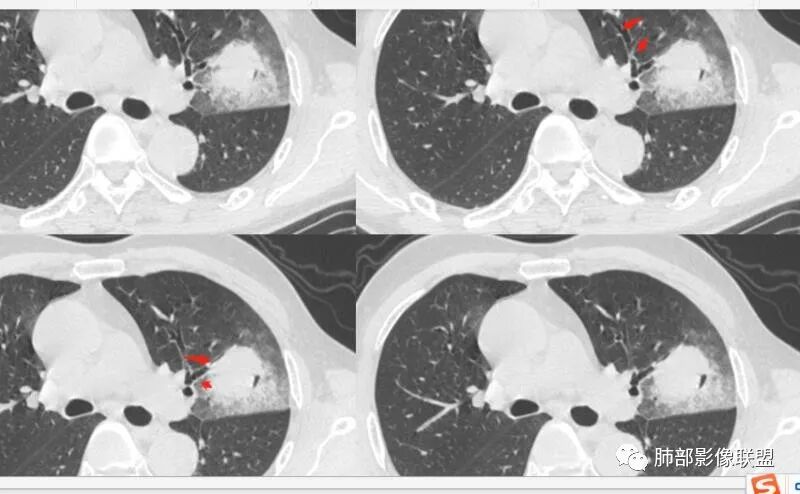

这三个月后的

发了后面这个,就不用纠结了,直接秒了。

我只是要告诉大家,不是二元,就是肿瘤,没有什么感染,磨玻璃都没消失。

1、团片状,实行密度区外观整体圆顿,位于上叶尖后段与下舌段区间。局部膨隆,但未见分叶,肿瘤多见。

2、偏心空腔病灶,气腔略呈新月形,壁不规则,腔内结节相对密实,明显强化且不均,支持新生物而非曲菌球等。炎性空洞多有强化环。

3、病变强化较明显,其内隐约显示多发小斑片状无强化灶,可疑边界不清小灶坏死区。病灶内血管影浅淡、模糊不规则。

4、支气管改变:上舌段支气管远段延入部分稍示僵硬。尖后段见分支支气管阻塞,恶性多见。

5、周围磨玻璃,3个月后逐渐转为密实,应符合当初附壁生长为主,且逐渐向实体成分转换。

6、病变长轴平行且受限于胸膜,外围大内带小,符合外朝内发展病变。“腔内结节状明显强化”加之支气管改变有力支持新生物诊断。如此大范围边界不清的磨玻璃影让人浮想联翩。如此大范围病灶,肺门纵隔未见肿大淋巴结也让人意外。